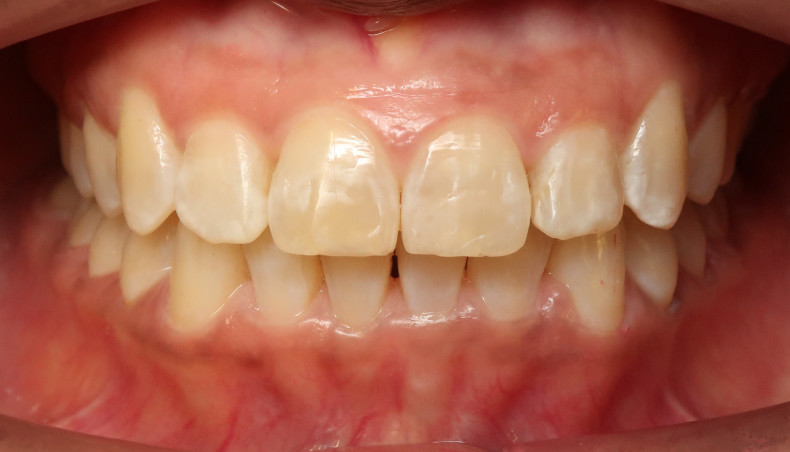

Nach dem Refinement konnte bei der Patientin sowohl eine beidseitige Neutralokklusion als auch eine deutliche Reduktion von Overjet und Overbite erzielt werden (Abb. 11a–c). Aufgrund des vormals ausgeprägten Frontengstandes und des Verzichts auf interdentale Schmelzreduktion blieb im Bereich der Zähne 31/41 ein schwarzes Dreieck bestehen (Abb. 11c), welches mit einem geringfügigen Kompositaufbau noch beseitigt werden könnte. An dem Zahn 11 wurde der Schneidekantendefekt mit Komposit versorgt (Abb. 13a und b).